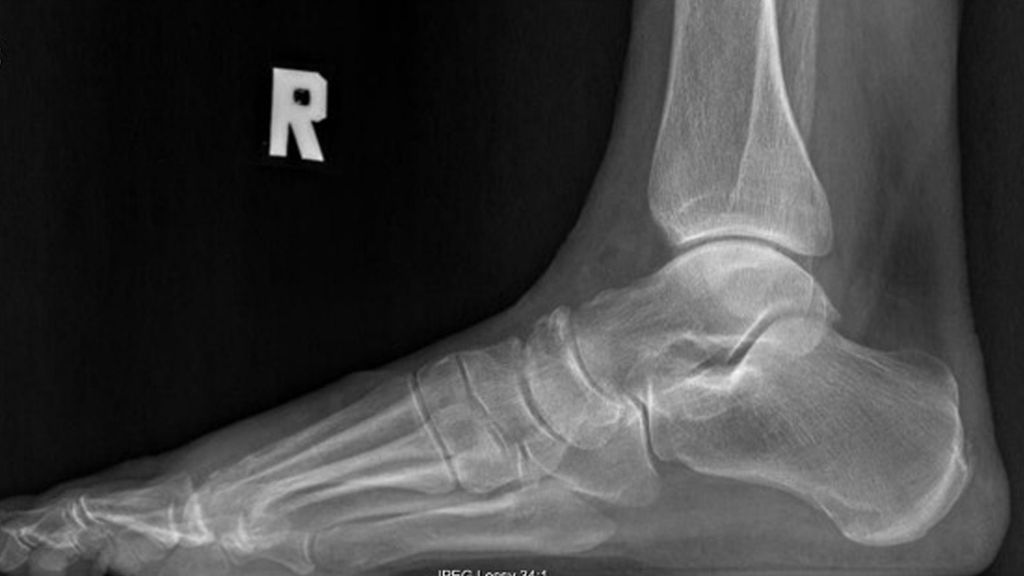

Symptome wie Schmerzen, die bei Belastung aggravieren, und Gelenkssteife sind häufig assoziiert mit der Entstehung eines dorsalen Osteophyten am MT1, welcher zu einem knöchernen Impingement führt (struktureller Hallux rigidus). Bevor eine gelenkerhaltende operative Behandlung des HR indiziert wird, sollten eine fokussierte klinische Untersuchung und die Analyse des lateralen belasteten Röntgenbildes erfolgen.

Die radiologische Abklärung beinhaltet belastete Röntgenaufnahmen des Fußes in a/p und seitlichem Strahlengang. CT und MRT haben keinen Stellenwert bei der Standardabklärung.